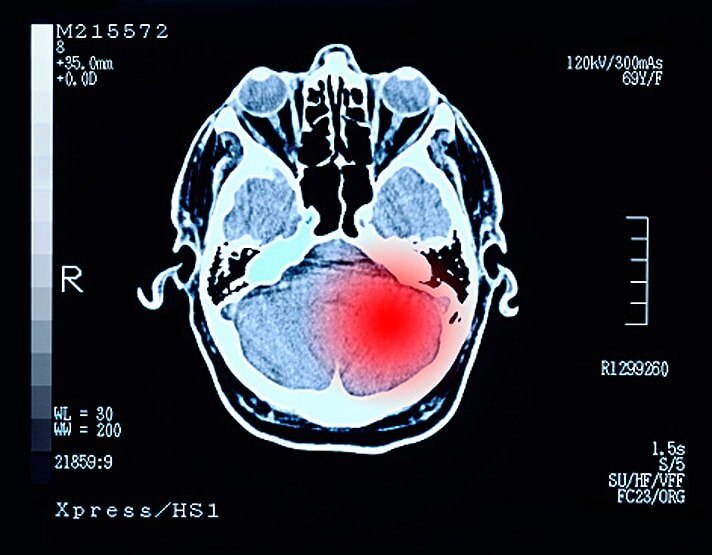

एड्रियन ने बताया कि कोरोना की वजह से लोगों के दिमाग में सूजन आ रही है. यह सूजन दुर्लभ है. इसे एक्यूट डिसेमिनेटेड इंसिफेलोमाइलिटिस (ADEM) कहते हैं. यह ज्यादातर युवाओं और बच्चों में देखने को मिल रही है. (फोटोः गेटी)

इस स्टडी को करने वाले वैज्ञानिकों ने बताया कि उन्हें हर महीने एक मरीज ADEM का शिकार मिल रहा है. लेकिन पिछले एक हफ्ते में इस बीमारी से ग्रसित लोगों की संख्या में तेजी से इजाफा हुआ है. (फोटोः गेटी)